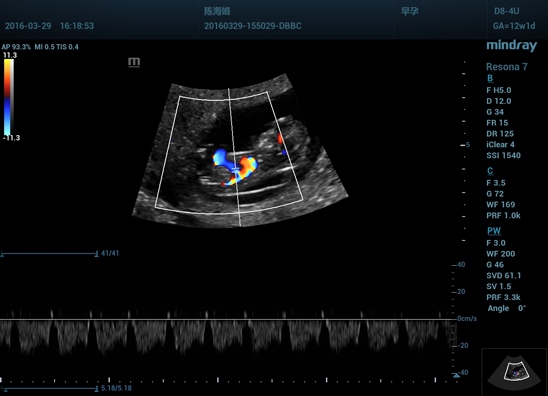

• Технология iClear: более четкое отображение краев и контуров; однородное качество изображения; заметное снижение уровня зернистости в областях без эхо-сигнала.

• Функция iTouch: мгновенная автоматическая оптимизация изображения в режиме B-режима, цветном и импульсно-волновом доплере с помощью одной кнопки.

Цветовой допплер:

Да

Импульсно-волновой допплер:

• энергетический и направленный доплер (Power и DirPower);

• импульсно-волновой доплер (PW);